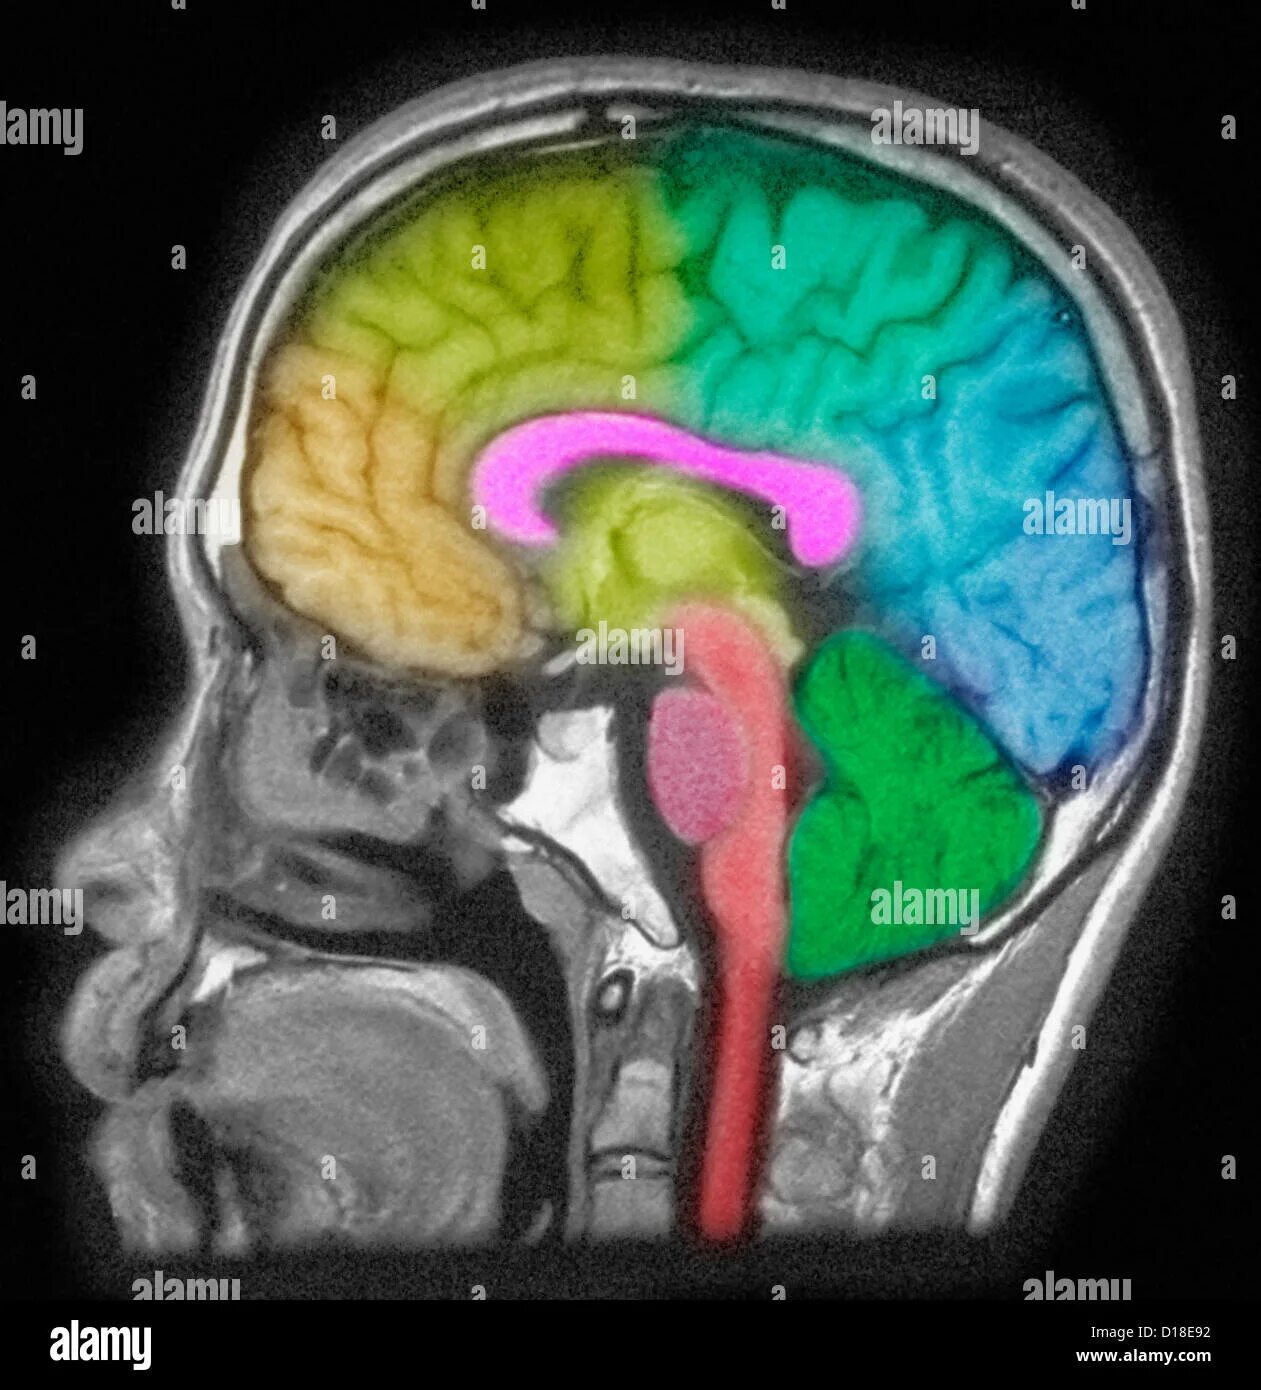

Sleeping brains